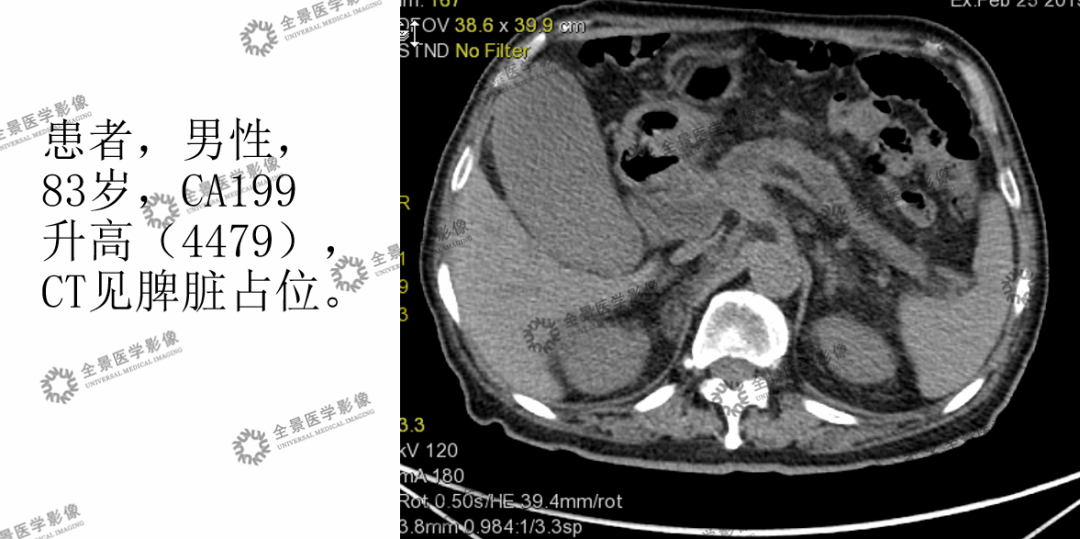

(2)肿瘤标志物升高查原因